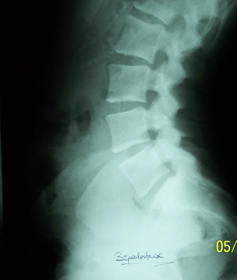

Estudio radiológico de columna vertebral en bipedestación

1) TRx AP de columna vertebral                                               2) Rx lateral de columna lumbar

• Rx lateral de col. Lumbar en BPD

• Normal    35%

• Hiperlordosis   27%

• Espondilolisis  9%

• Anomalías de transición 5%

• Apofisitis vertebrales 4%